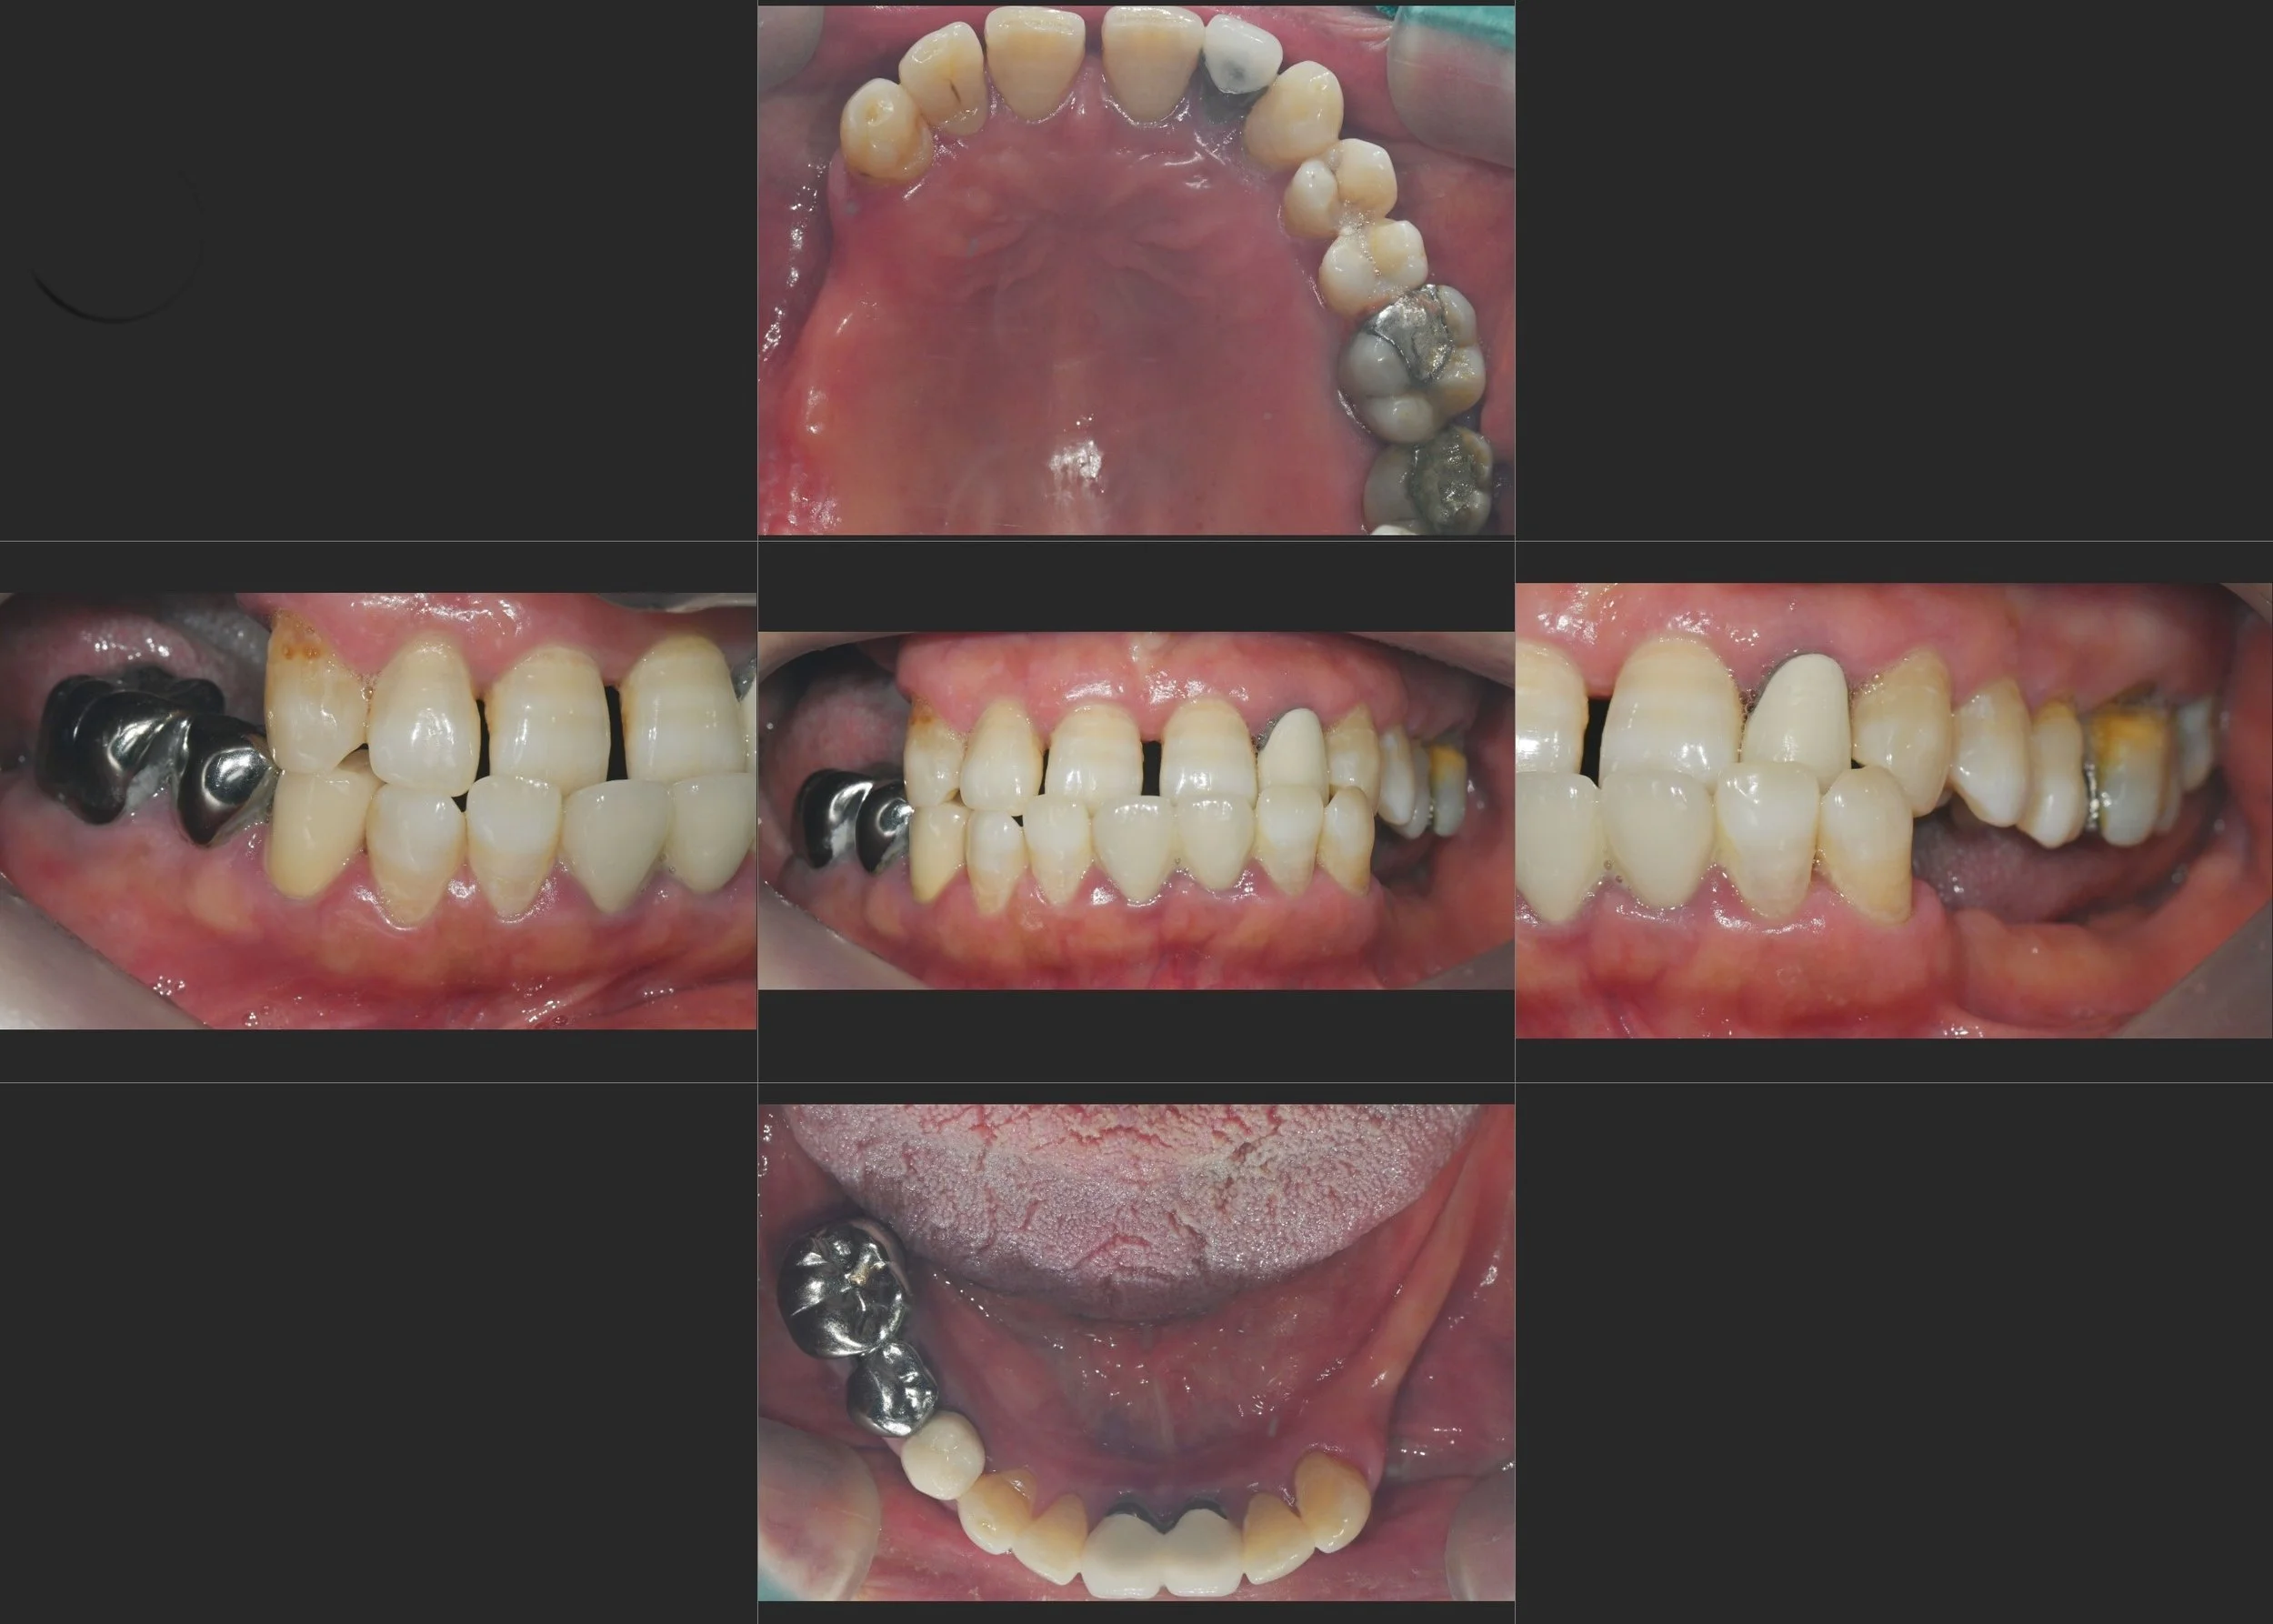

35. Comprehensive Full-Arch Transformation: Restoring Confidence in a Young Phobic Patient

Reversing the effects of generalized rampant caries and occlusal collapse in a female patient in her 20s. A tooth-preserving, implant-assisted approach focused on stable VDO elevation and overcoming social anxiety.